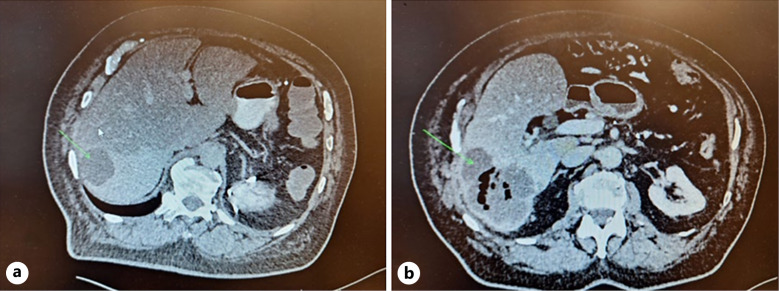

Case presentation: A 70-year-old male presented with weight loss and abdominal pain in July 2018, was diagnosed with stage IB PDAC (pT2, pN0, M0), and underwent successful R0 resection. Adjuvant chemotherapy with FOLFIRINOX (5-FU, LV, irinotecan, and oxaliplatin) was given for 9 cycles between September 2018 and January 2019, and the patient remained recurrence-free until a computed tomography scan revealed soft tissue mesenteric infiltrations in July 2020. First-line palliative chemotherapy with nab-paclitaxel + gemcitabine was initiated and continued until January 2022 when disease progression in the form of two metastatic hepatic lesions was observed. Second-line palliative chemotherapy with nal-IRI 129 mg on day 1 + capecitabine (CAP) 4,000 mg daily for the first 7 days of each 14-day cycle was initiated (due to previous 5-FU intolerance). Response (reduced oncomarkers) was observed, and treatment with nal-IRI + CAP continued, with liver-directed treatment in September 2023, until February 2024. During second-line therapy, side effects (mild diarrhoea) were infrequent and manageable.

Abstract Image